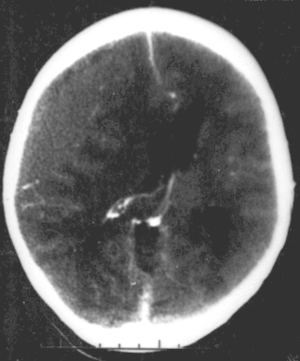

| Nontraumatic epidural hematoma in a young woman. The grey area in the top left is organizing hematoma, causing midline shift and compression of the ventricle. | |

قد تبدي الصورة البسيطة للجمجمة وجود كسر. لكن الاختبار الأمثل للتشخيص هو التصوير الطبقي المحوري للدماغ CT.scan، فهو يُظهر النزف على شكل منطقة عالية الكثافة محدبة من الجهتين ومحاذية للجمجمة.